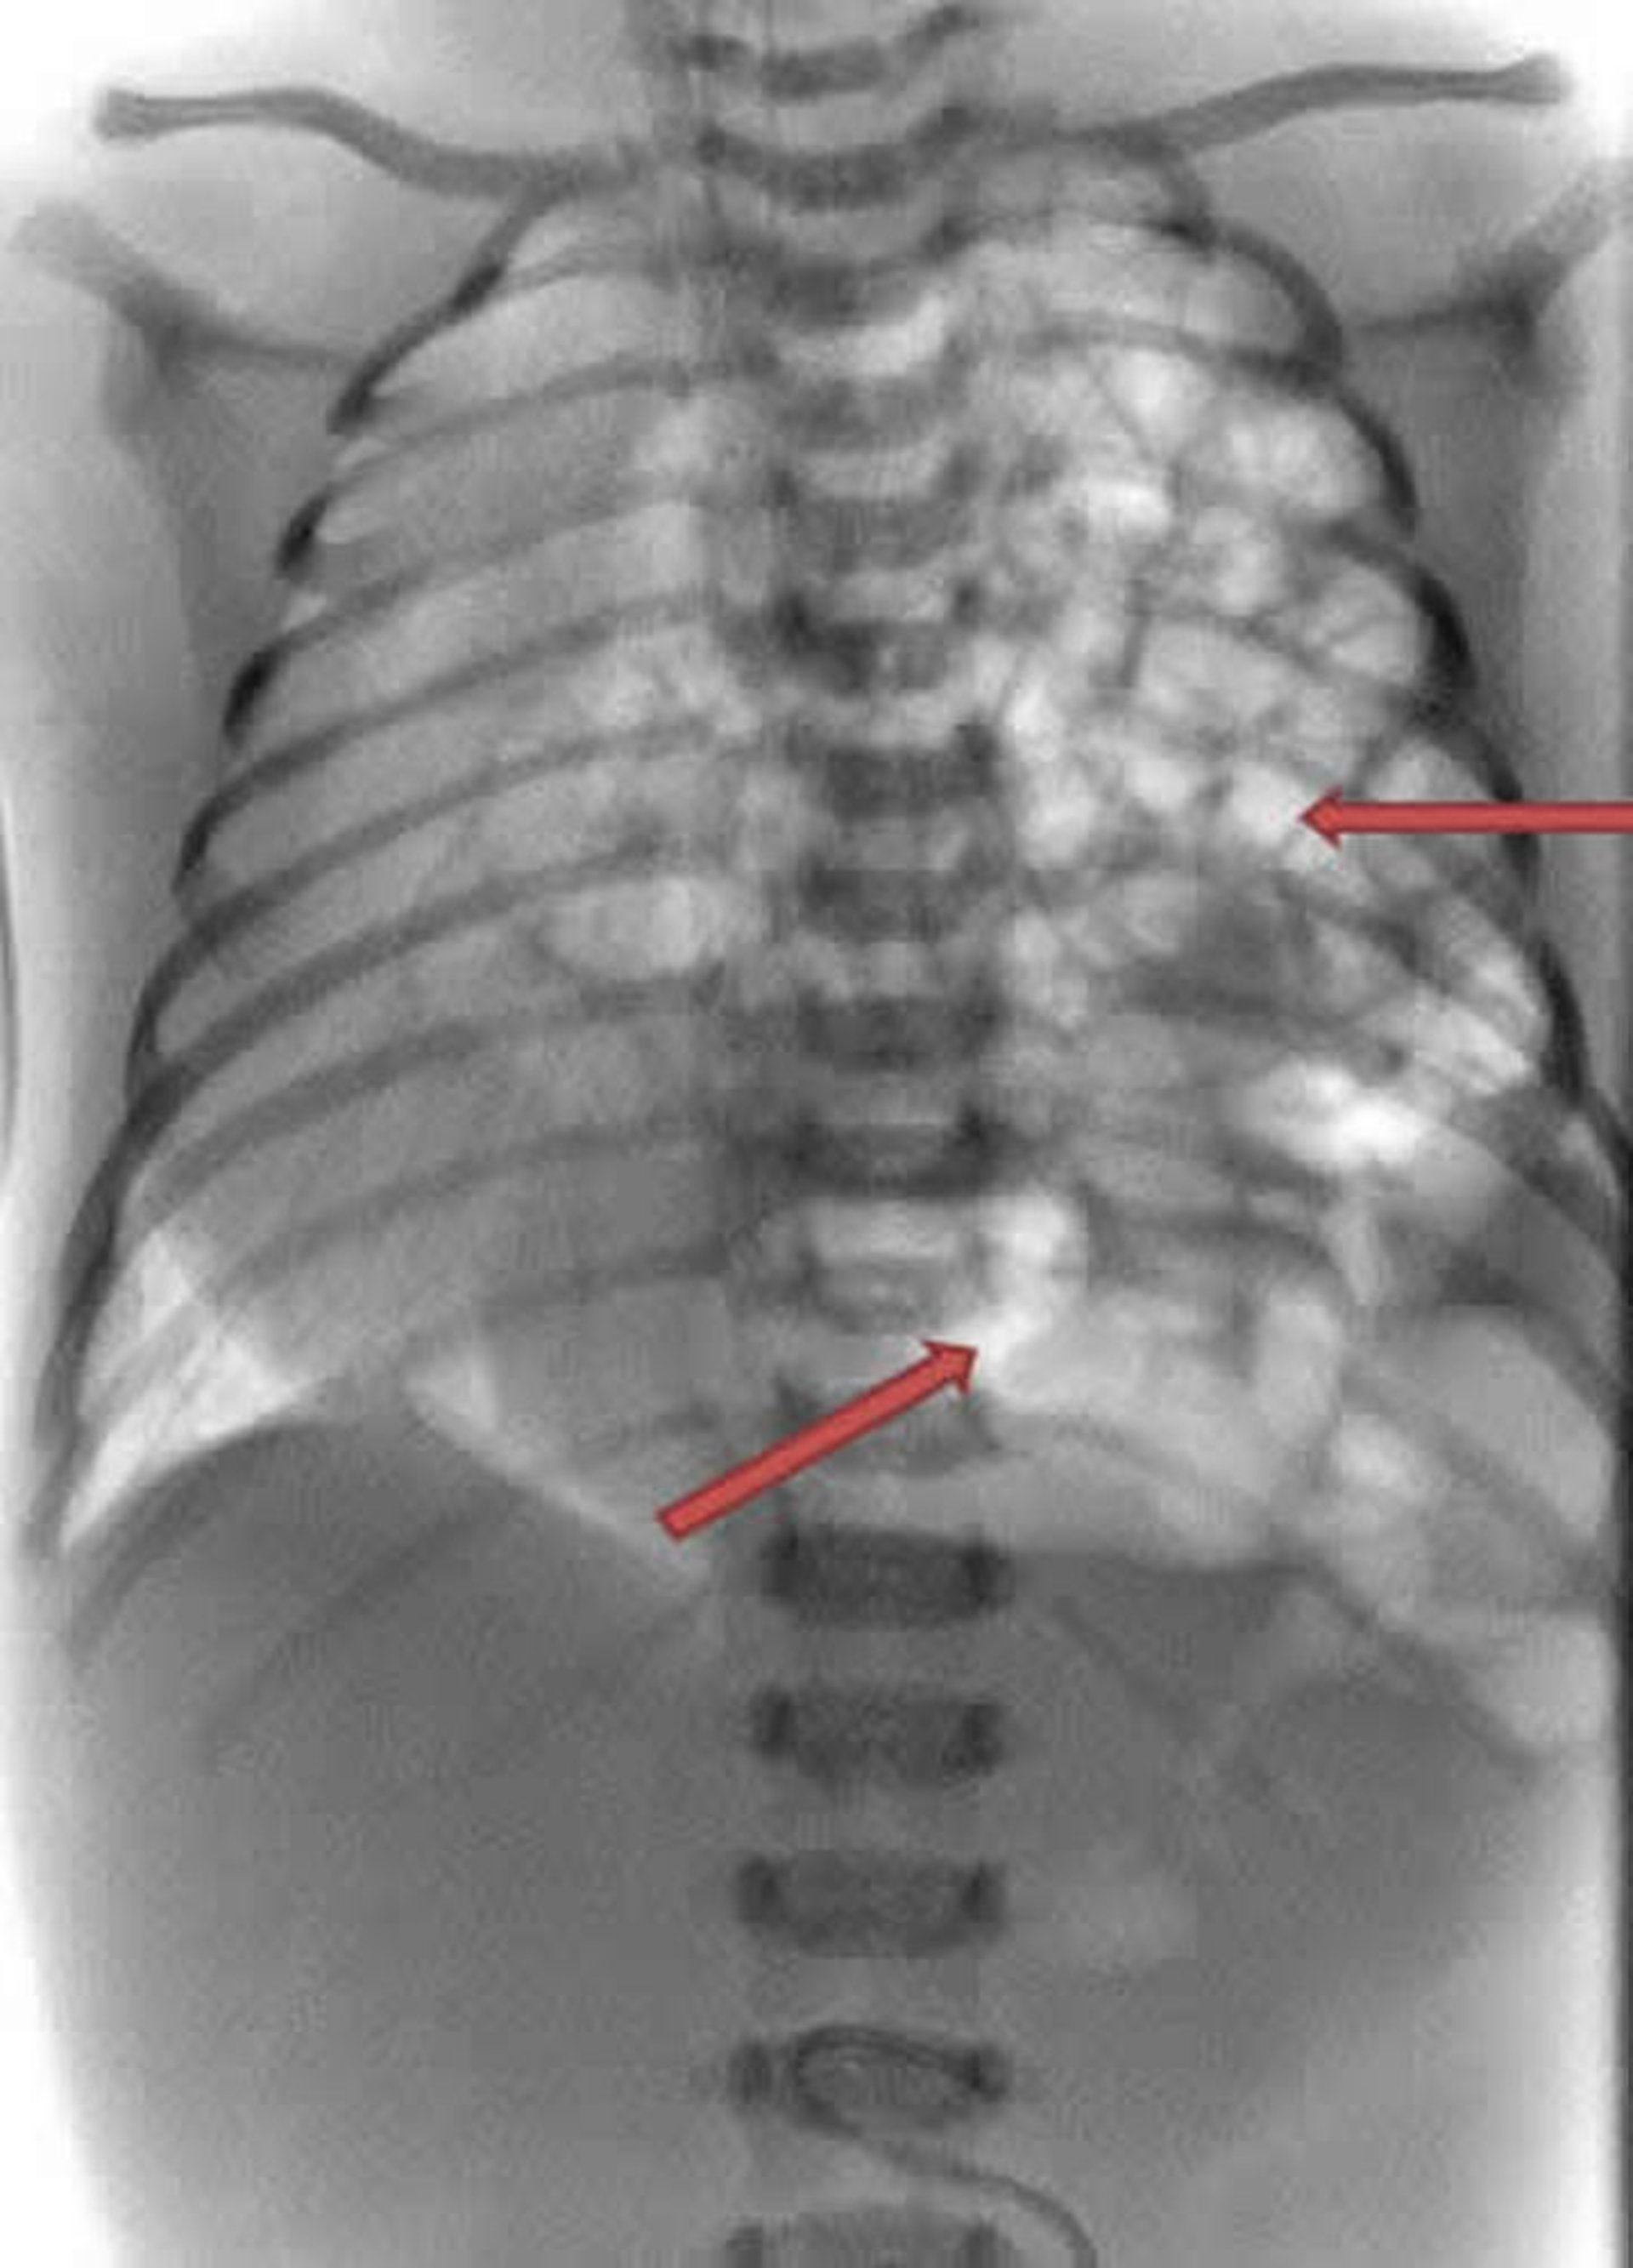

This x-ray of a newborn shows the intestines (white coils) are protruding into the left side of the chest (arrows).